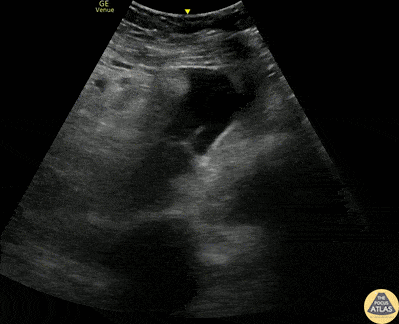

Trauma - Pelvic +FAST from Spleen Lac

20s F presented with presyncopal episode after standing electric scooter crash. She had been evaluated at an urgent care where she had dental injuries identified, but was initially hemodynamically stable. She arrived to the ED tachycardic and hypotensive, and FAST exam was positive in the pelvic view as shown here in transverse and sagittal orientations. She was resuscitated with massive transfusion protocol and responded well. CT scanning showed a grade 2 splenic laceration. The patient was admitted for further observation and serial CBC checks. Dr. Larry Benjey, PGY-3 Denver Health Residency in Emergency Medicine